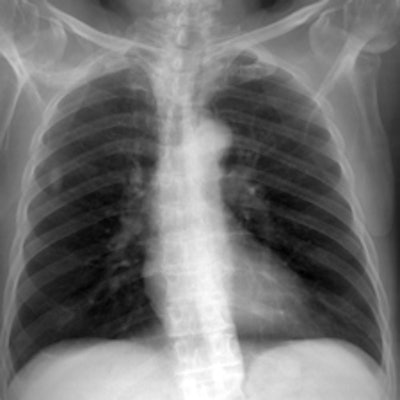

Simulated chest images of an average-sized patient reconstructed with an antiscatter grid (a) and without a grid (b). Image (a) provides greater detail, especially in the denser regions of the chest, which is expected."Although there is a trend toward increased image quality at low tube potentials, it was only possible to statistically distinguish between 50 and 90 kVp, 80 and 90 kVp, and 80 and 109 kVp," Moore and colleagues wrote. "All other combinations demonstrated p-values > 0.102. Nevertheless, these results show that for matched effective dose, image quality improves with lower tube potentials, which is similar to results reported in the literature."

However, to compensate for the reduced intensity of the x-ray photons, an increase in mAs would be needed, they noted.

For average adult patients, low tube potentials (102 kVp) and no scatter rejection provide superior image quality, according to the researchers.

"However, it has been shown that for obese adult patients an oscillating focused antiscatter grid is indicated, and should be used in conjunction with as low a tube potential as possible, as this combination provides superior image quality to any other investigated during this study," they stated.